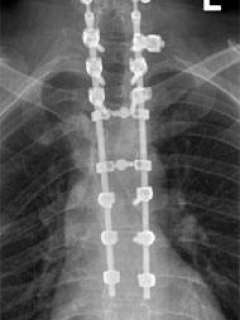

X-ray of Jim's spine with sixteen titanium screws and two rods

I made the decision that he would need to undergo extensive surgery, simultaneously treating the fractures in his neck and mid-back. I had a long talk with his wife regarding the procedure. We used computer image guidance, a cutting edge technology in which placement of the bone screws were guided by a computer workstation. He required two surgeries, and a total of sixteen titanium screws and two rods were placed (Fig. 2). His spine was fused from the C5-T8 levels.

X-ray of Jim's spine with two rods clearly visible